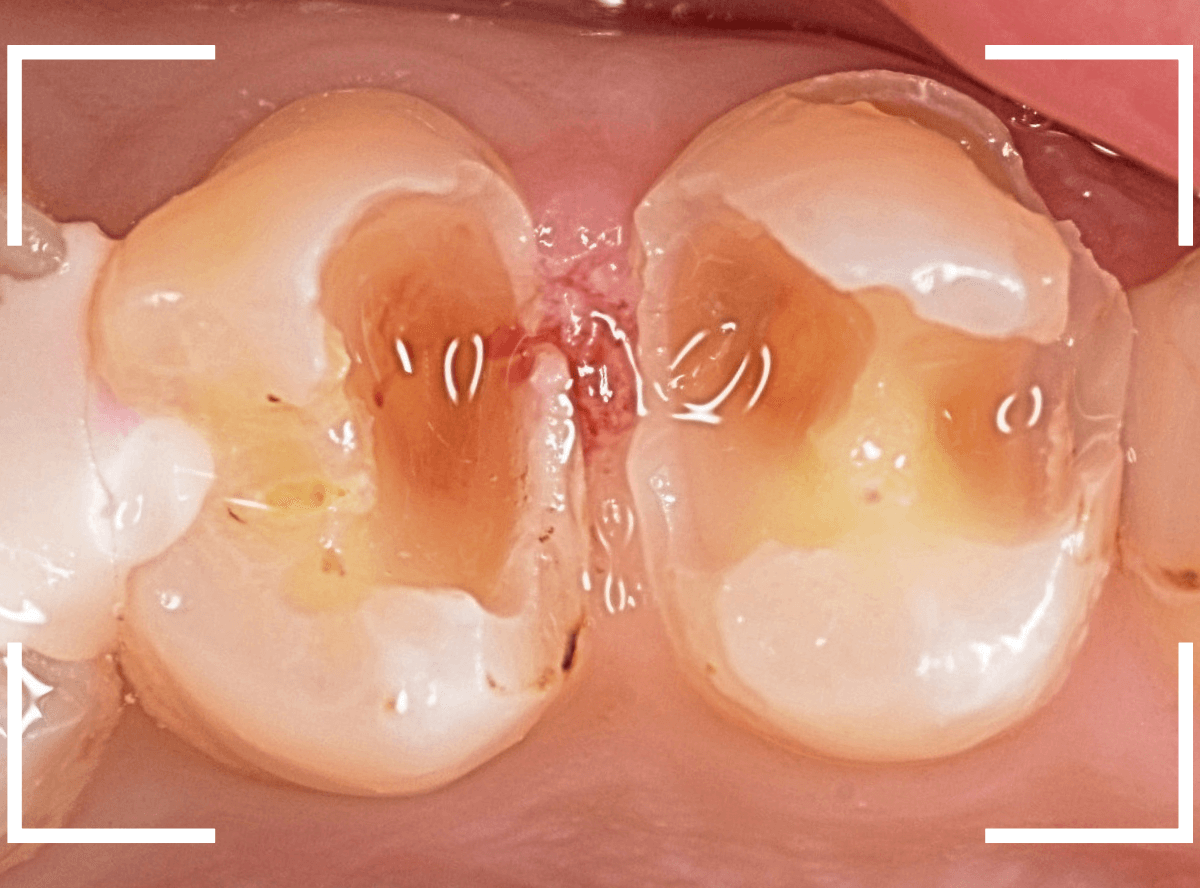

Case.1 隣り合った2本が大きな虫歯

「下の歯の奥から2番目の歯が痛む」という患者さんです。

お口の中を拝見すると、何だか1番奥の歯も怪しそうなので、歯を叩いて症状を確認してみます(打診)。

やっぱり奥から2番目の歯が痛むけど、1番奥の歯も少し痛むそうです。

レントゲン写真で確認してみました。

やはりどちらの歯も大きな虫歯でした。

2番目の歯が痛みの原因なのかもしれませんが、1番奥の歯の可能性も大いにあります。

両方の歯が原因かもしれません。

いずれにせよ、両歯とも痛みを神経に近い虫歯ですので、神経が炎症を起こして本格的な痛みになる前に治療をして神経の治療(抜髄)にならない可能性を少しでも上げたいところです。

通常であれば、初診時に大きな虫歯治療を2本行う時間的な余裕もありませんので、患者さんに事情を説明して後日治療になるのですが、今回は、予約時間よりも余裕をもって早めに来院していただいた患者さんだったので、何とか当日治療まで進める事ができました♪

まずは、麻酔をしてつめ物を慎重に外してみます。

両歯とも、色々嫌な予感のする所見です。

虫歯を可視化する、「う蝕検知液」で染め出ししてみます。

赤く染まっている場所が虫歯で、濃く染まっているところほど、虫歯は深いです。

手前の歯は一部神経が見えそうなところまで虫歯が来ていました(●部)。

患者さんのおっしゃるように、この歯が痛みの原因だったのかもしれません。

後ろの歯も、幸い神経は見えていませんが、かなり広く深い虫歯で心配な状況です。

急いで、神経を保護する薬を入れた後に、セメントで蓋をして経過観察します。

ほとんどの方はこれで何とかなりますが、痛みが出てしまい、神経の治療が必要になる方もいます。

神経の治療をすると歯の寿命は短くなってしまうので、できるだけ避けたいところです。

慎重に経過観察します。